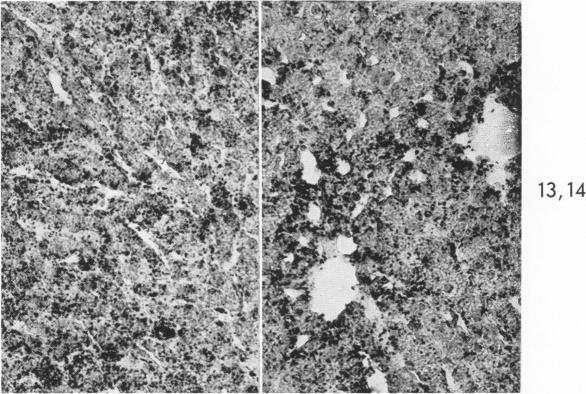

RESPONSE OF THE LIVER TO "TARGET" IRRADIATION.

Am J Pathol. 1965 Sep;47(3):339-51.